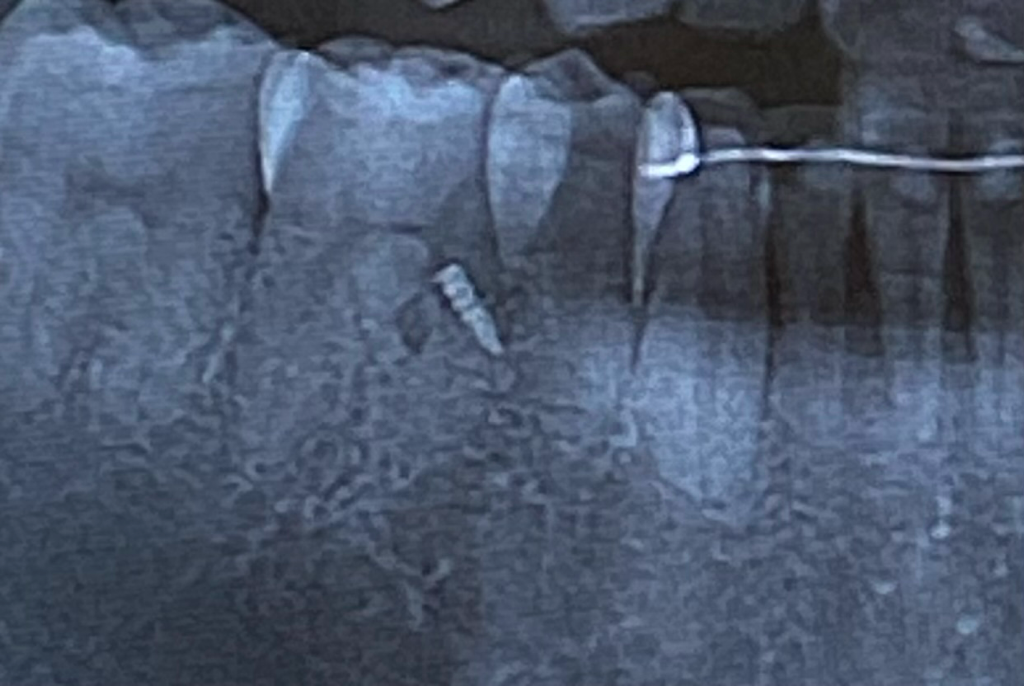

교정을 마무리한지 2년정도 되었습니다. 그런데 최근 치아 교정으로 인한 기능적인 불편함이 생겨서 재교정을 위하여 다른 치과 방문 후 x-ray를 찍어보니 교정 보조장치인 미니스크류가 부러진채로 그대로 잇몸 안에 박혀있다는 이야기를 들었습니다.

수술적 방법으로만 제거가 가능한 상태이고 CT추가 촬영 이후 소견으로는 제거를 하다가 치아 뿌리에 손상을 줄 수 있는 위치라고 합니다.